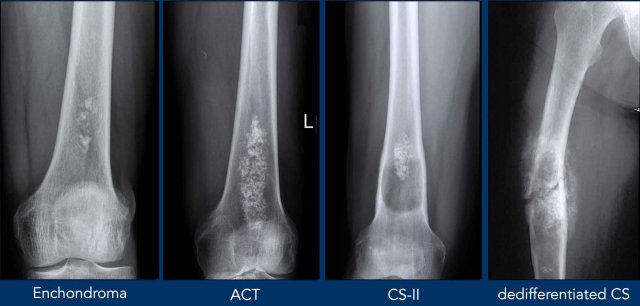

Terminology in Chondroid tumors

This figure demonstrates

examples to explain the terminology used to describe chondroid tumors.

In some examples there can

be more than one typical finding.

X-ray

On radiographs, chondroid tumors show

foci of nodular, popcorn-like matrix mineralization.

These calcifications may be present within the entire spectrum of

chondroid tumors.

Often the tumor

size is underestimated on a radiograph, as frequently only the mineralized part of the

tumor is visible.

In the phalanges, enchondromas may present as purely osteolytic tumors, not necessarily containing matrix calcifications.

Image

There is a small area of 1.5 cm with popcorn calcifications in the distal metaphysis of the femur without extension to the cortex.

This is an enchondroma.

Images

The radiograph demonstrates an

osteolytic lesion in the distal femur containing typical popcorn calcifications

and showing anterior cortical scalloping (arrowhead).

On the sagittal MRI we can appreciate

that the tumor is larger than the area of calcifications on the radiograph,

measuring 8 cm.

The tumor is hyperintense on T2 STIR and contains multiple foci

of low signal intensity, corresponding to the chondroid matrix calcifications

on the radiograph.

Conclusion

Since there is no periosteal reaction or soft tissue mass, these findings fit with the diagnosis of ACT.

The patient remains in follow-up.